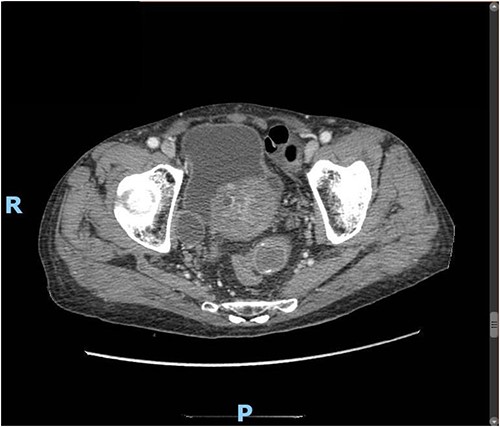

Upon clinical examination, the patient was vitally stable. Abdominal examination revealed a distended abdomen with generalized tenderness. Digital rectal examination revealed an empty rectum with no palpable masses. Laboratory investigations were unremarkable (Table 1). Abdominal X-ray was done (Fig. 2) and showed dilated large bowel loops suggestive of bowel obstruction. Enhanced CT scan of the abdomen and pelvis was obtained (Figs 3–5) and showed a dilated large bowel loop, with air fluid level. A 2.5-cm gallstone was noted, impacting the sigmoid colon and causing partial large bowel obstruction. There was evidence of pneumobilia with air foci within the gallbladder with a suspected fistula with the hepatic flexure.

Enhanced CT scan of the abdomen showing evidence of partial large bowel with pneumobilia, gallbladder seen with interrupted wall and suspected fistula with the hepatic flexure (axial view).